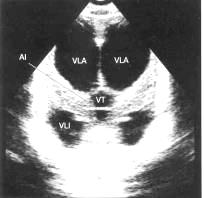

Ультразвукове дослідження головного

мозку (нейросонографія) - це звичайне, недороге обстеження, що допомагає

оцінити ступінь розширення шлуночків мозку. Звукові хвилі проходять через

незаросле тім'ячко, даючи чітку картину шлуночків, що значно полегшує

постановку діагнозу. У старших дітей УЗД не використовується, кістки черепа

перешкоджають проходженню ультразвуку. Виключення складають випадки, коли існує

дефект черепа - отвір, через який можуть проходити звукові хвилі. Метод УЗД

використовується також для внутрішньоутробної діагностики гідроцефалії. Ц,ь,ю)